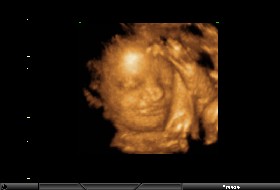

mamamocorgó: szóval neked írnám hogy én holnapi napon töltöm be a 22.hetemet,és én már időnként érzek rugdosást,de legkevésbé sem rendszeresen...

bizony van hogy 1-2 napig semmi,meg olyan is van hogy egy nap már 15-ször is éreztem...és amikor érzem őt,az még mindig reggel és este van/volt,ágyban vízszintesen fekve,és erősen koncentrálva.Szóval ne aggódj nem csak nálad jönnek azok a mozgások nehezen.Türelem és egyszer te is érezni fogod!!

Ja és nekem is vastag a hasfalam,mivel nem voltam már terhesség előtt sem pehelysúlyú,és ráadásul a 18hetes UH-on a méhlepényemet is mellső falinak írták,és ráadásul harántfekvésben van a kisbabám.Szóval minden tényező adott nálam is hogy nehezebben érezzem...